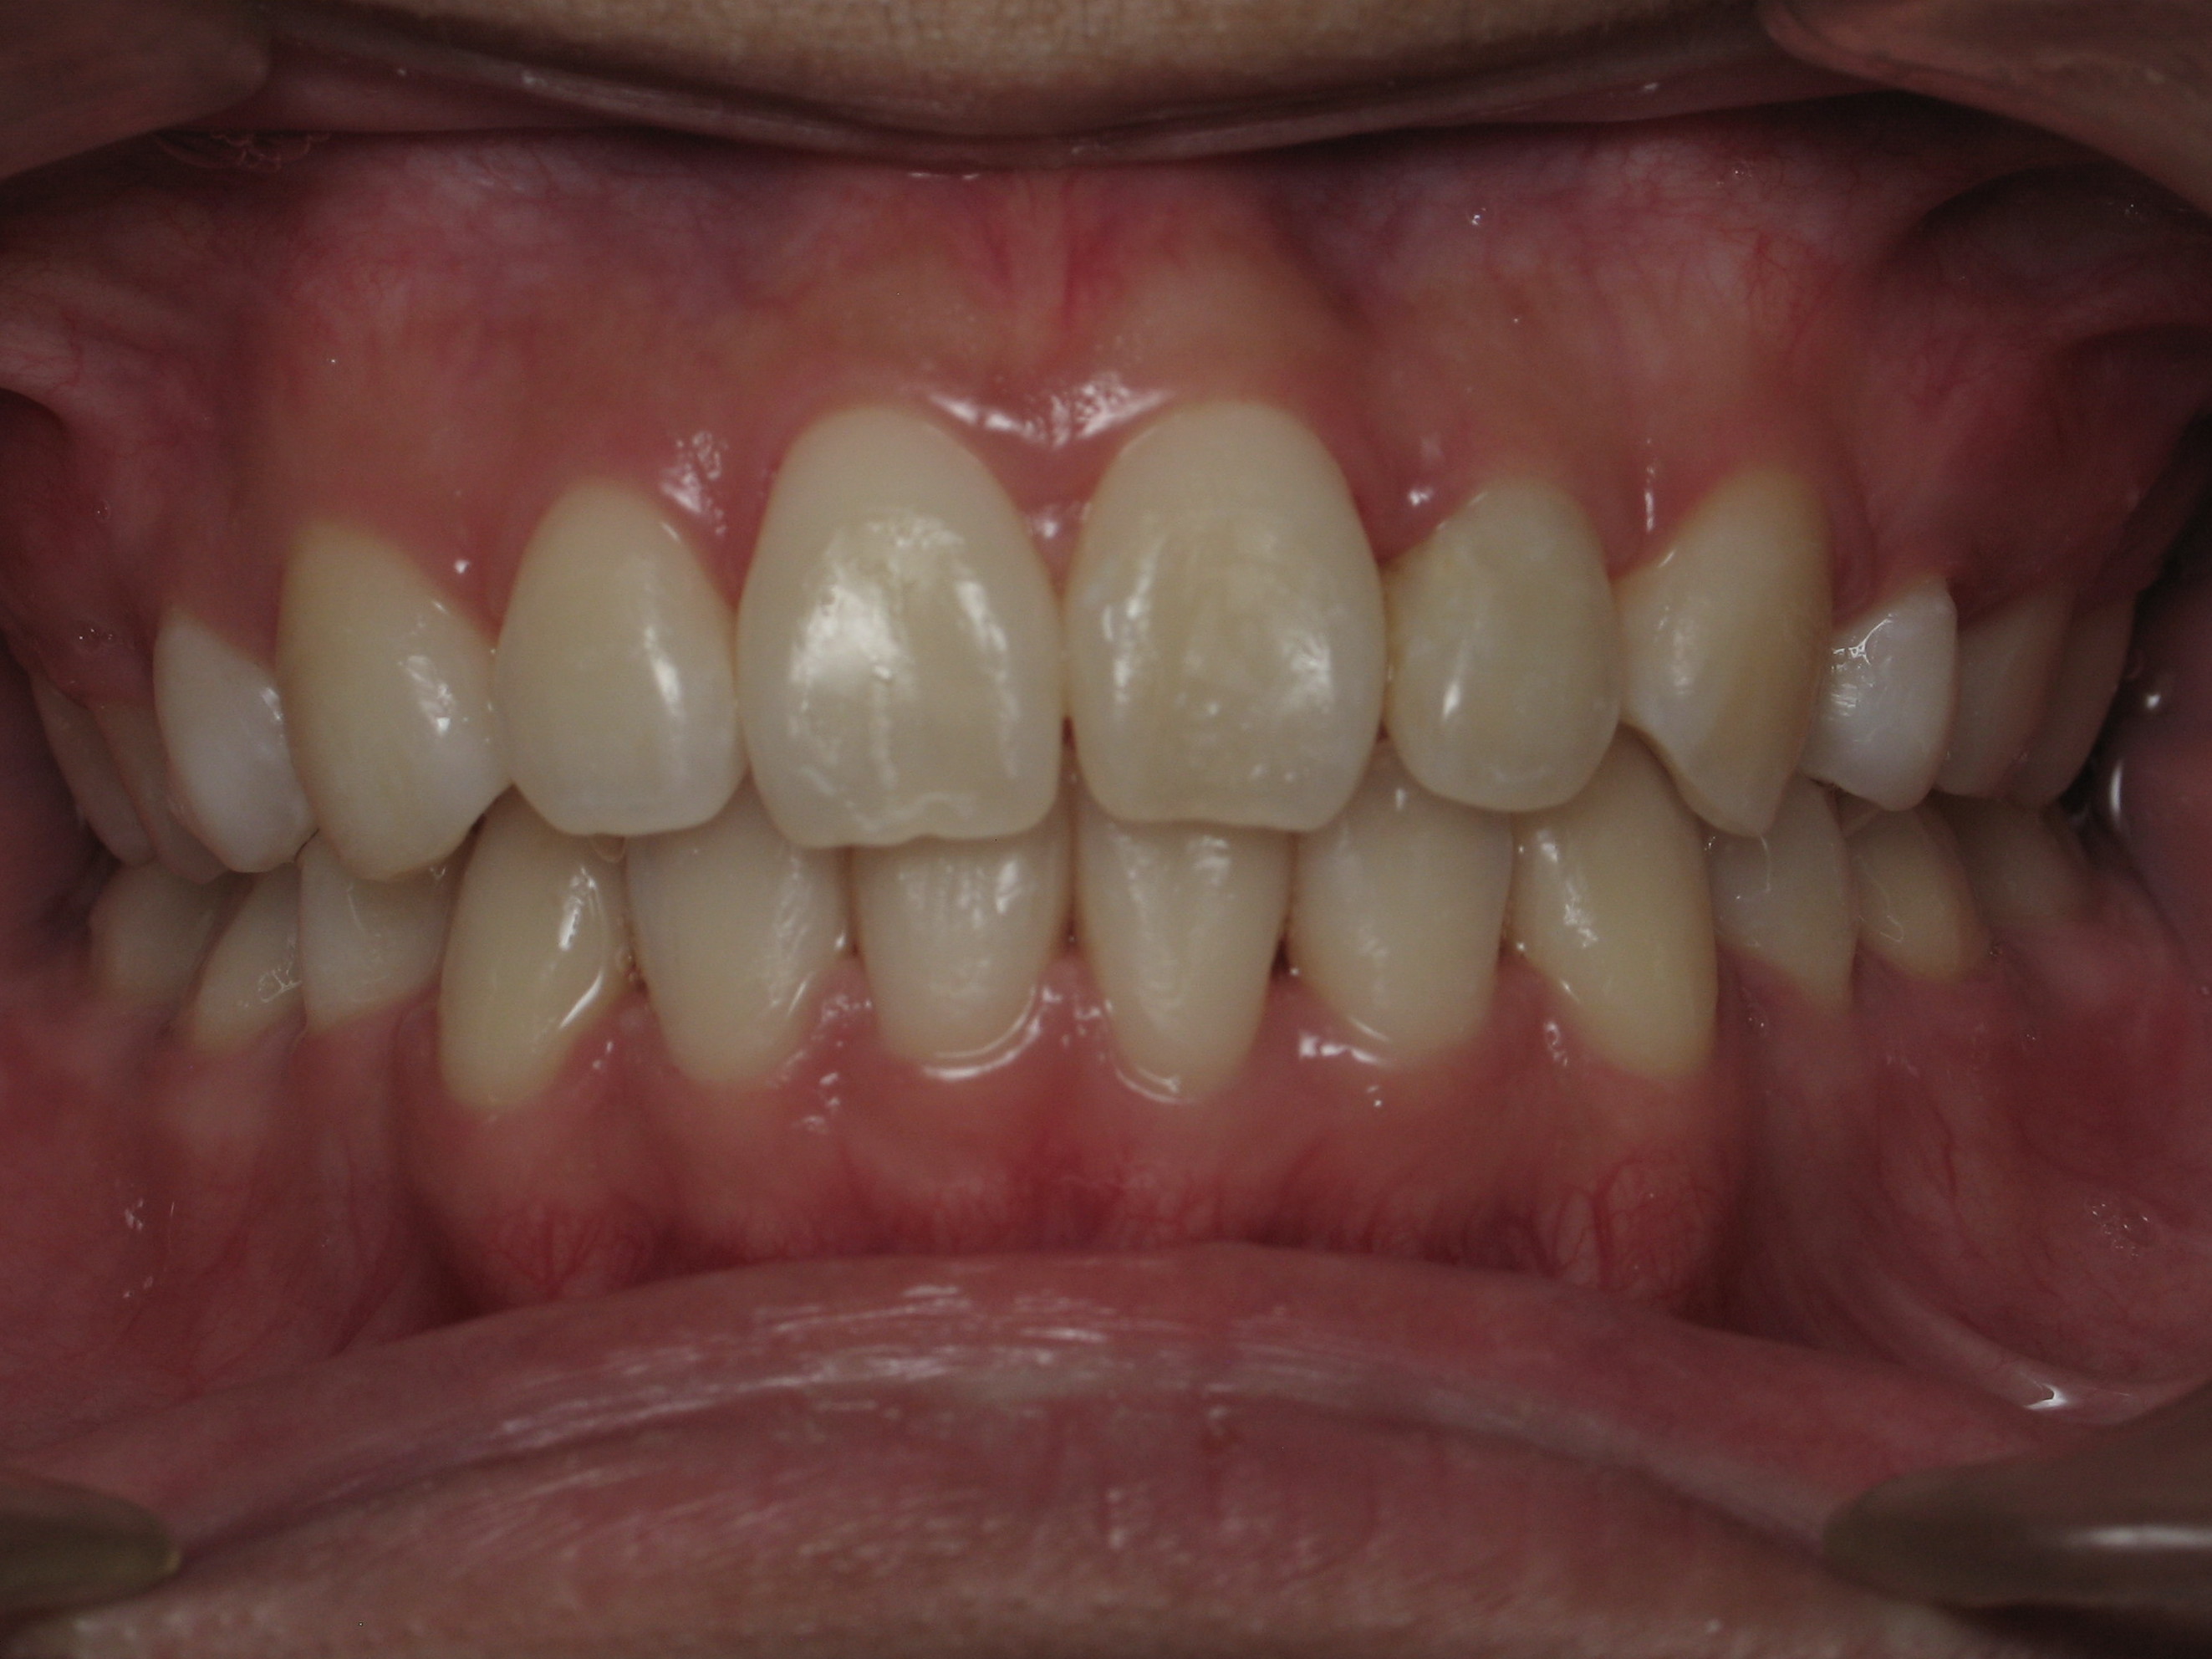

Smile Gallery

Ready to Start Ortho Treatment